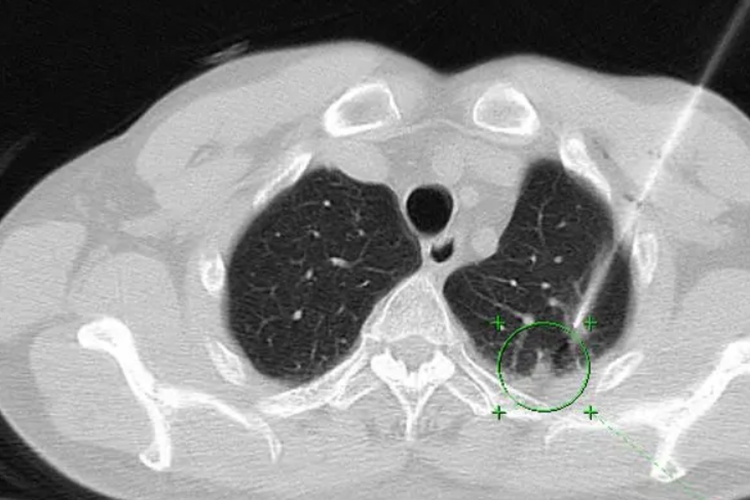

表现为两肺弥漫性随机分布的结节或多发球形病灶,边缘光滑,密度均匀,以中下肺野及胸膜下区较多见。少数转移瘤可呈现空洞、气囊或发生钙化。HRCT对经淋巴路径的转移瘤诊断有独特的优势,除见肺门及纵隔淋巴结增大外,还可见小叶间隔不规则增厚和沿支气管血管束、小叶间隔分布的多发细小结节影,呈“串珠样”改变。